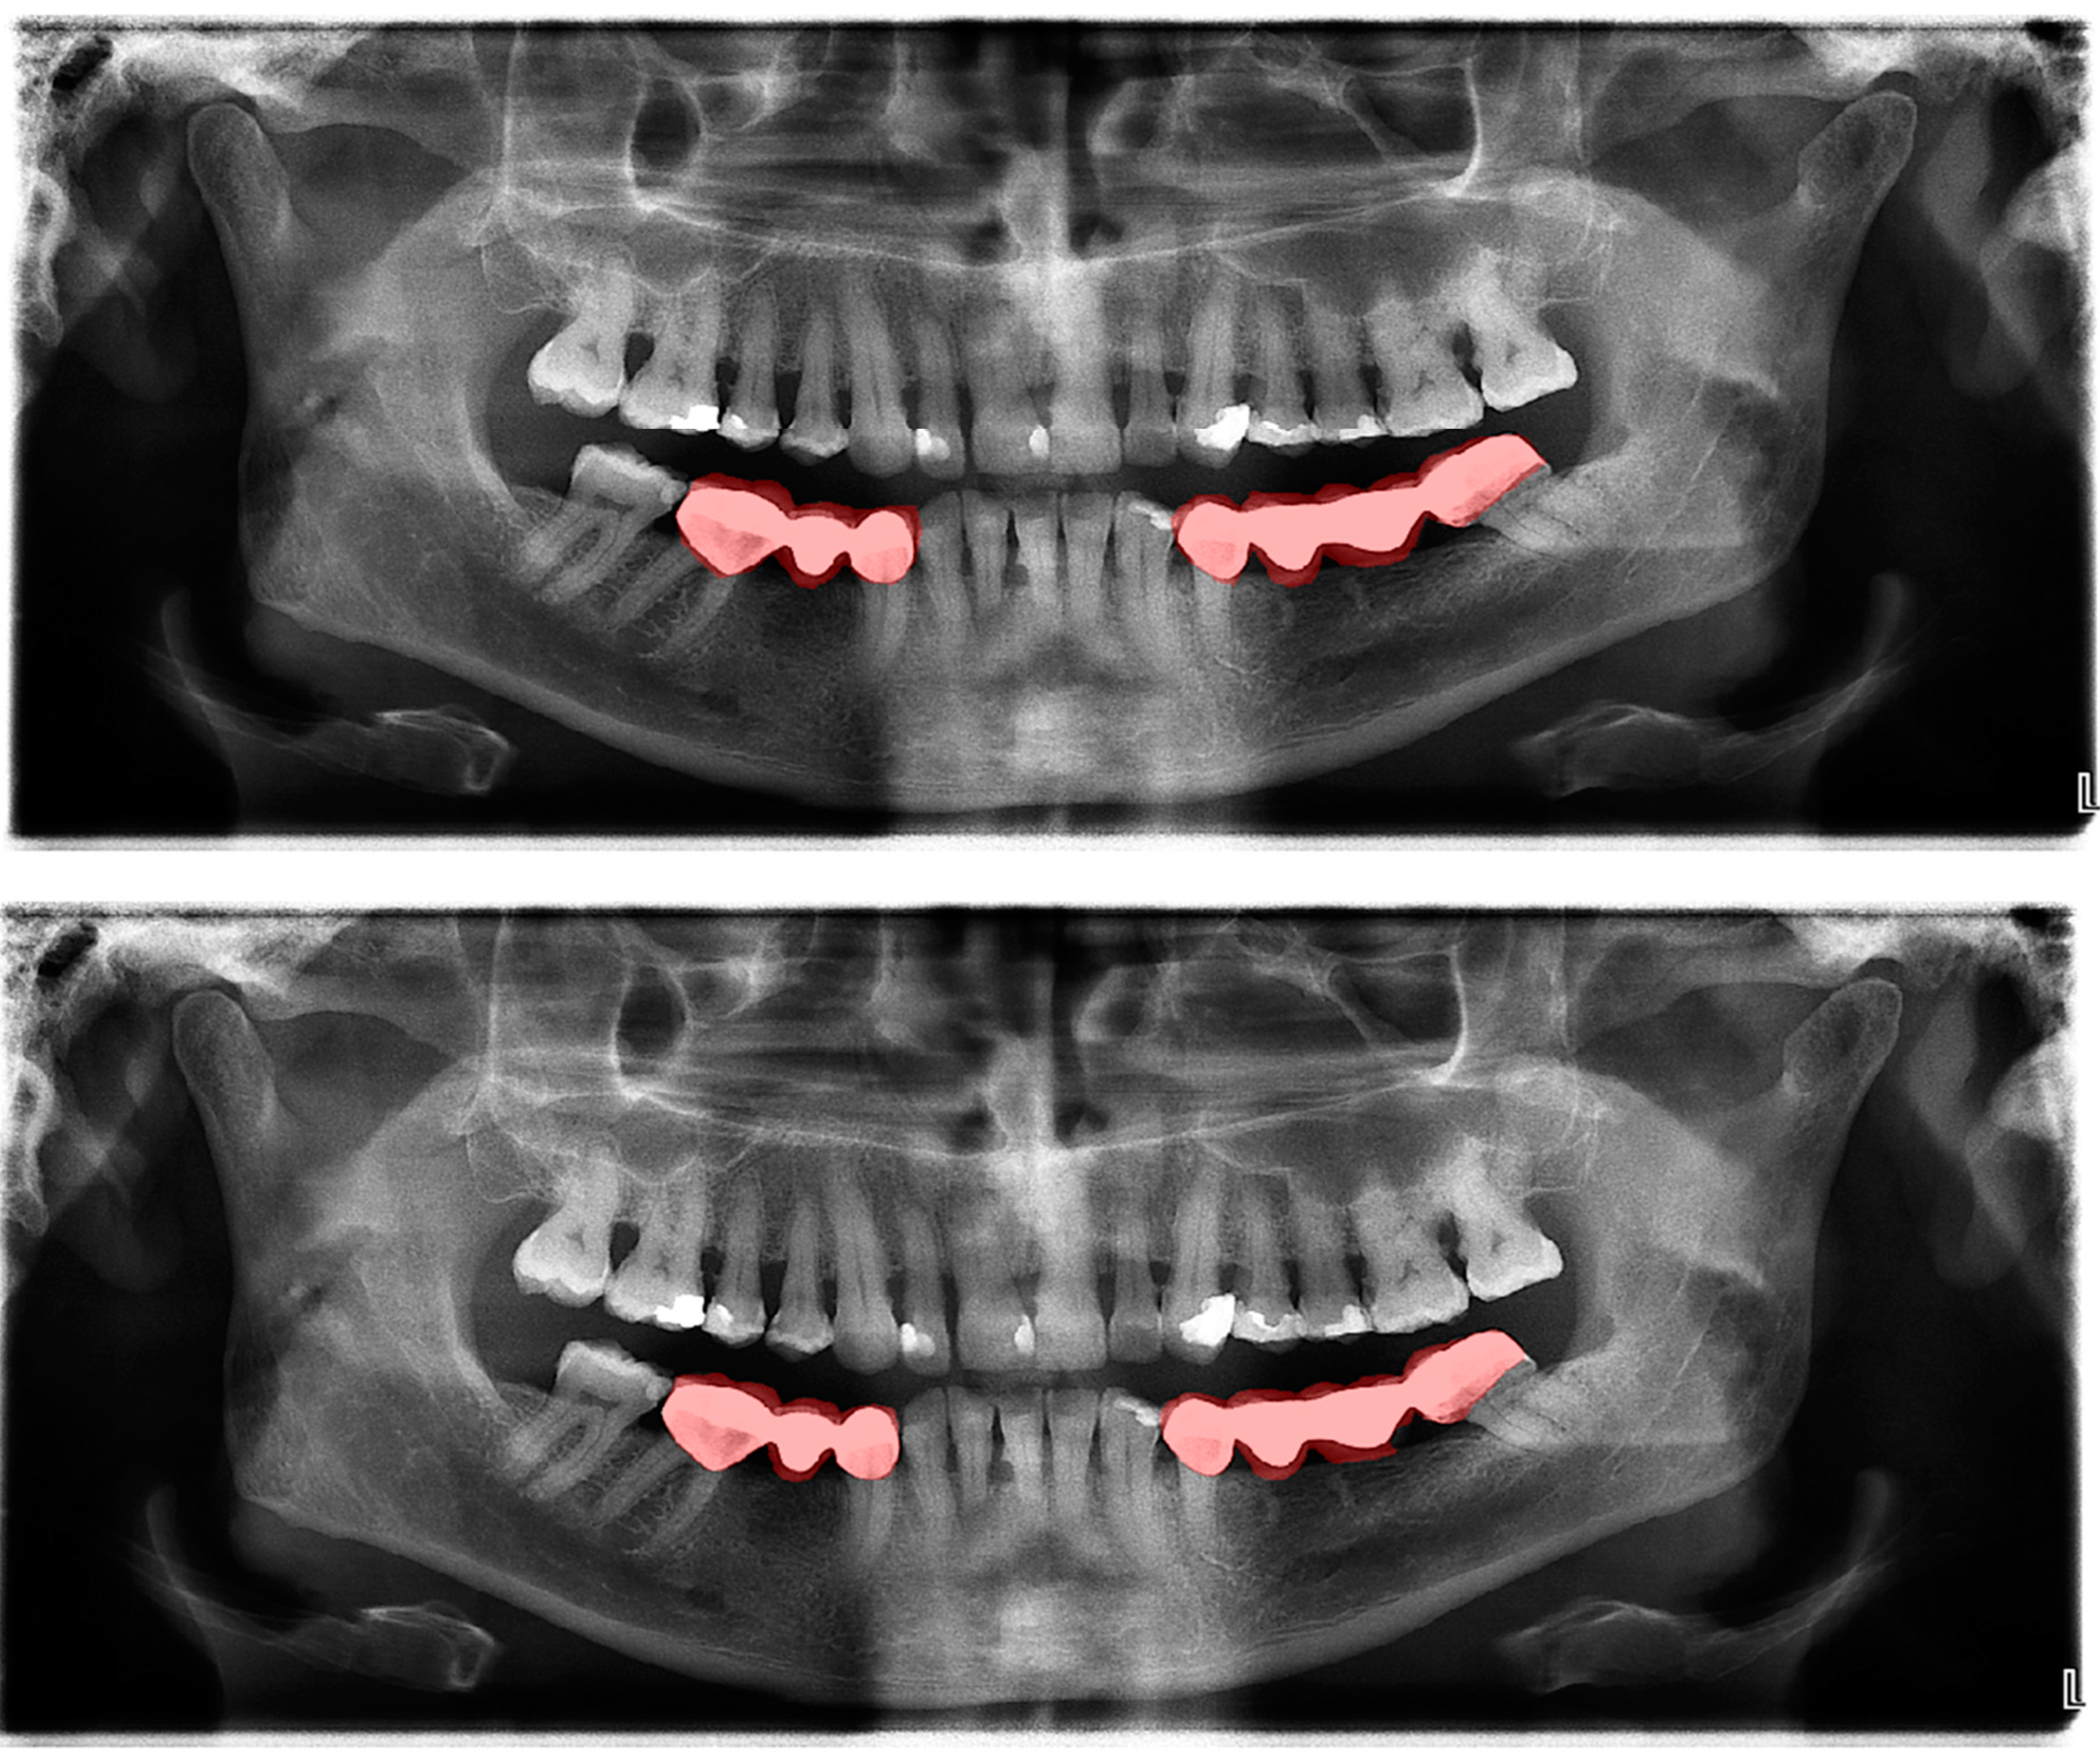

| Structure | DSC |

|---|---|

| Dental caries (Figure 3) | 0.88 |